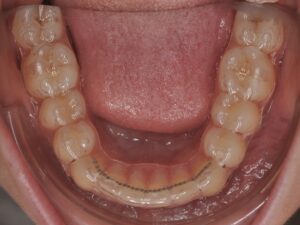

- d’un fil collé sur la face interne (linguale) des dents

- de gouttières passives de stabilisation réalisées sur mesure. `

Les gouttières passives de stabilisation sont à porter toutes les nuits la première année puis une à deux fois par semaine tout au long de votre vie.

Le fil de contention quant à lui est fixe. Idéalement, il est à garder toute votre vie également.